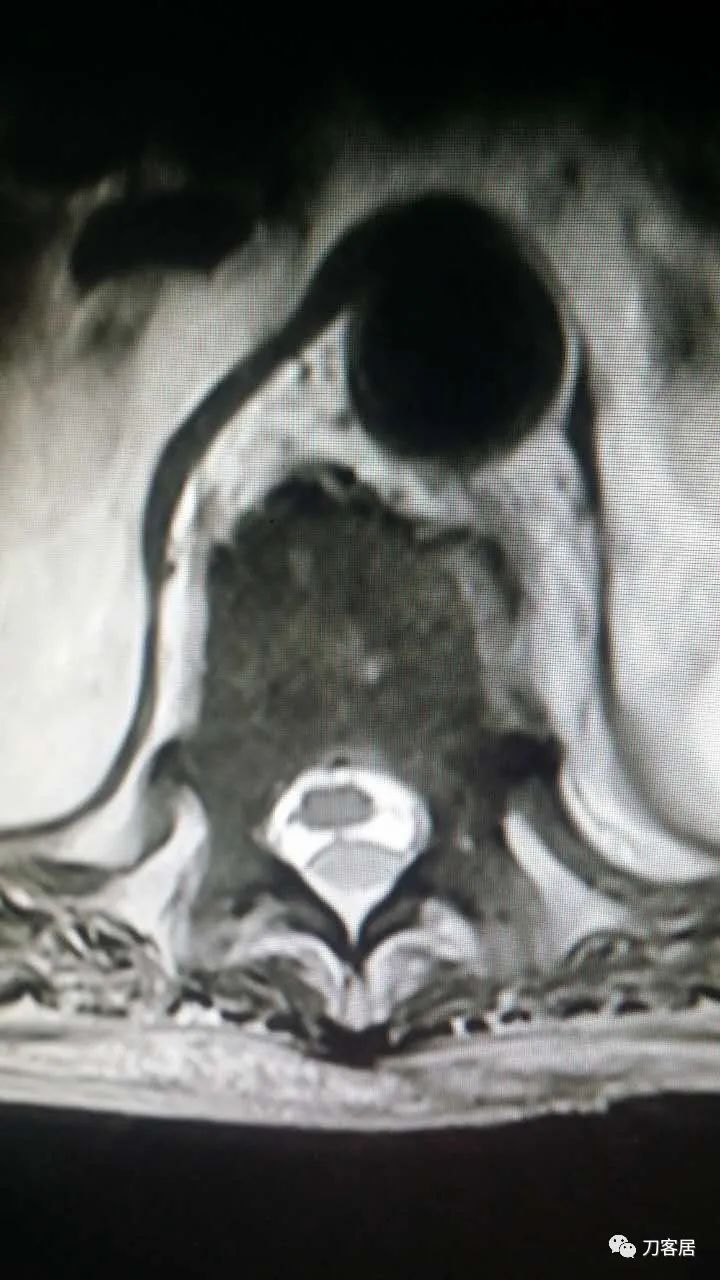

加注图14. 胸9-10椎管内后方高信号占位病变,考虑血肿形成。

加注图15. 胸9-10椎管内后方高信号占位病变,考虑血肿形成。

加注图16. 胸9-10椎管内后方高信号占位病变,考虑血肿形成。

加注图17. 胸9-10椎管内后方高信号占位病变,考虑血肿形成。